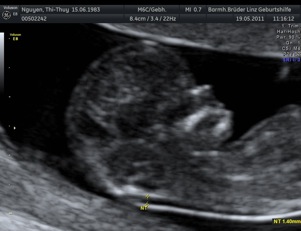

* First Trimester Screening. Messung der Nackentransparenz, Nasenbein, Combined Test (12.-14. SSW) - hier Termin vereinbaren!

2. Organscreening idealerweise in der 22.-24. SSW - hier Termin vereinbaren!